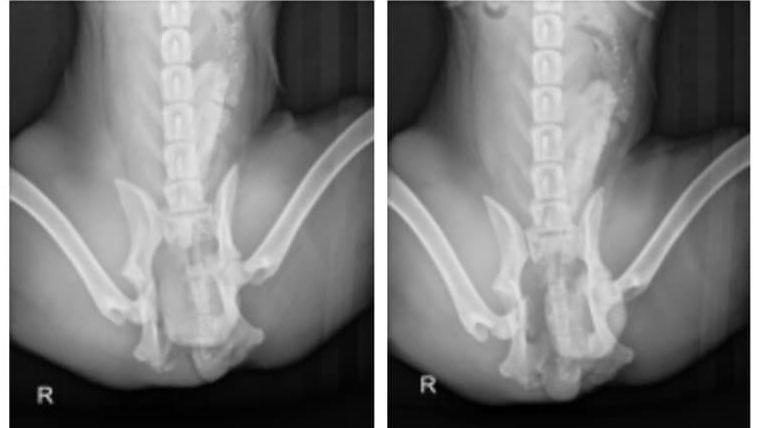

They further stabilized him, took x-rays, and did a few tests.

Then the bad news arrived: He had a fractured pelvis and a broken femur, and the staff recommended emergency FHO (Femoral Head Ostectomy) surgery.

He was hospitalized for 24 hours, and then they referred me to a low-cost clinic that was able to perform the surgery at a discounted price of $2,435.

Following an overnight hospitalization, we went ahead with the surgery, and he started his cage-rest rehabilitation the next day.